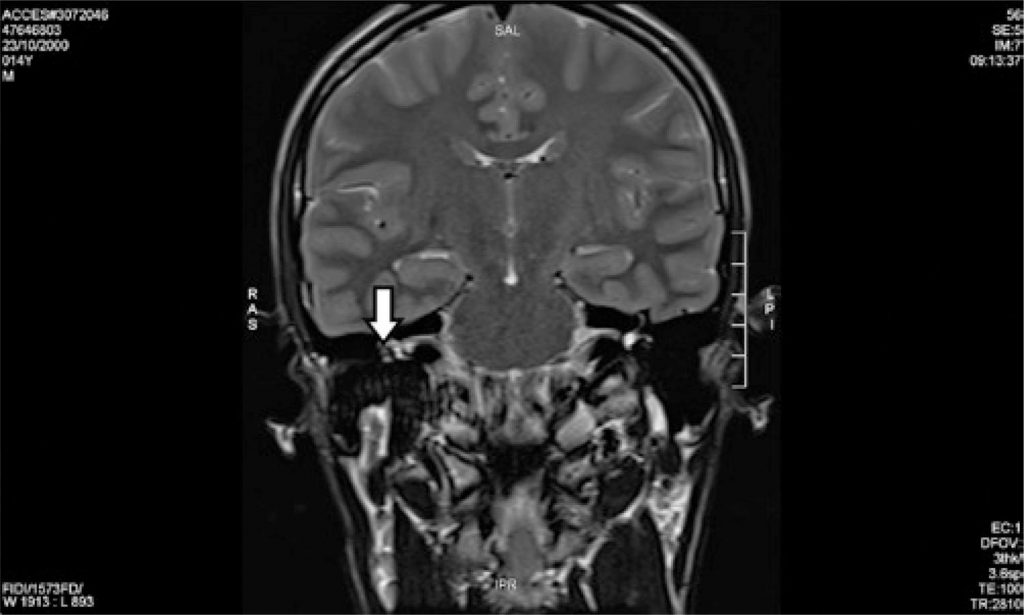

Facial nerve hemangioma is a rare and benign vascular tumor, and accounts for 0.7% of intratemporal tumors. We report the second case described in the literature of a facial nerve hemangioma in its tympanic segment. A 14-year-old male patient presented with a history of progressive right ear hearing loss with preserved facial mimicry. Pure tone audiometry showed a right ear moderate conductive hearing loss. Magnetic resonance imaging demonstrated an expansive lesion involving the tympanic segment of the right facial nerve, suggestive of hemangioma. Watchful waiting was chosen as management. In the first case of middle ear facial hemangioma described in the literature, facial palsy was the symptom that led the patient to seek medical care. In the present case, it can be inferred that the first symptom was conductive hearing loss ipsilateral to the lesion. Facial palsy may not be present and the clinical presentation may resemble otosclerosis, ossicular chain disruption, and third window abnormalities, among other differential diagnoses of conductive hearing loss. The second case of tympanic portion facial nerve hemangioma is reported, describing the specificity of conductive hearing loss as its only clinical manifestation.